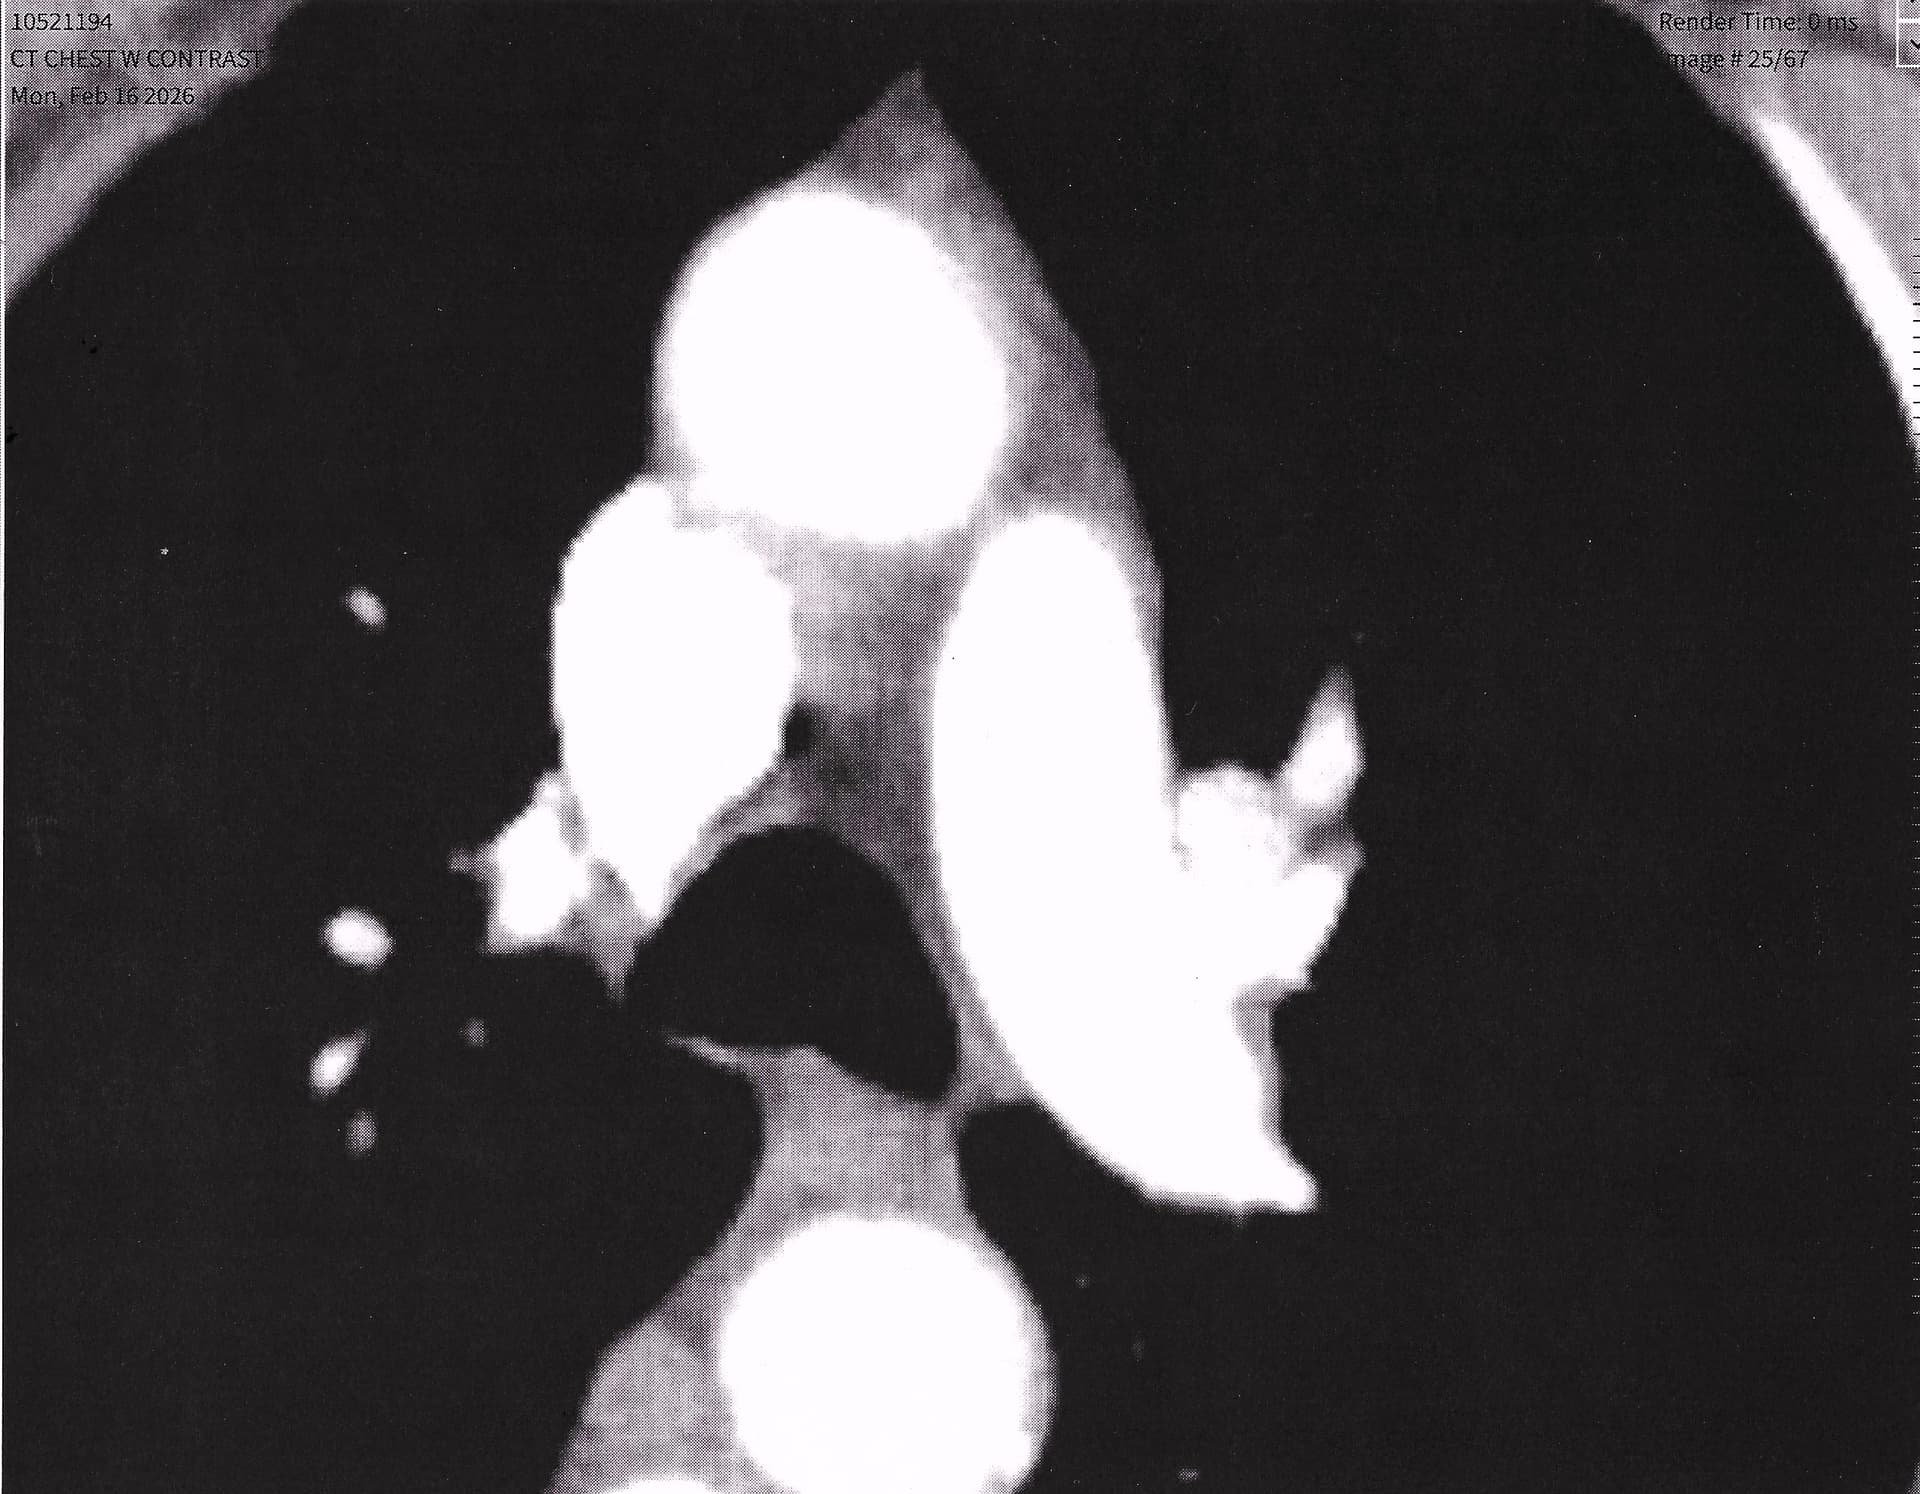

And now my thymus at the top - pic 25/67 and one layer down - cutting through it… pic 26/67 - it is big, full and fat free.

So there you are… now only using small HGH dose of 2 iu for maintenance every other day, a bit more when I feel skin damage or other body trauma needs a kick. Next to rapamycin – HGH is the best addition to my healthspan plan followed by TRT. In this order, Rapa, HGH, and TRT. I think all three are rocking me.